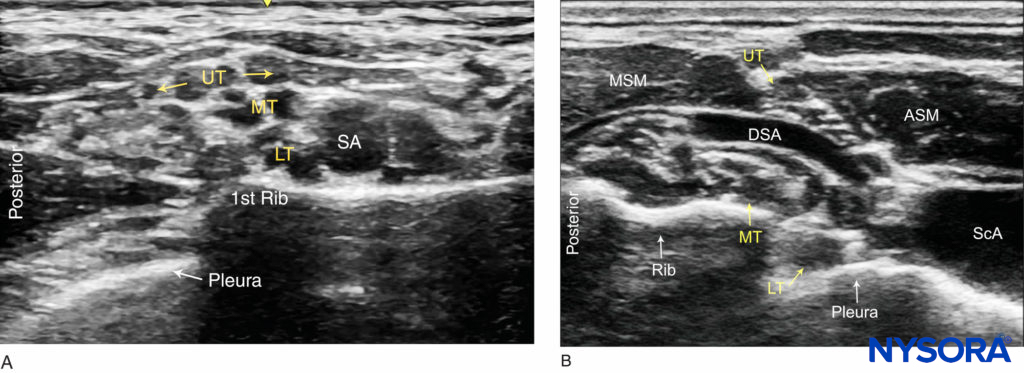

The subclavian artery crosses over the first rib between the insertions of the anterior and middle scalene muscles, posterior to the midpoint of the clavicle. The subclavian artery is readily apparent as an anechoic round structure, whereas the parietal pleura and the first rib can be seen as a linear hyperechoic structure immediately lateral and deep to the subclavian artery (Figure 3). The rib casts an acoustic shadow so that the image field deep to the rib appears anechoic.2 The brachial plexus can be seen as a bundle of hypoechoic round nodules just posterior and superficial to the artery (Figures 3 and 4). It is often possible to see the fascial sheath of the muscles surrounding the brachial plexus. Adjusting the transducer orientation, the upper, middle and lower trunks of the brachial plexus can be individually identified, as they join together at the costoclavicular space. To visualize the lower trunk, the transducer is oriented in the sagittal plane, until the first rib is seen deep to the plexus and the artery. (Figure 4). Anterior or posterior to the first rib is the hyperechoic pleura, with lung tissue deep to it. This structure can be confirmed by observing a “sliding” motion of the viscera pleura in synchrony with the patient’s respiration. The brachial plexus is typically visualized at a 1- to 2-cm depth at this location. The presence of two separate clusters of elements of the brachial plexus may be more or less obvious, sometimes with separation by a blood vessel (Figure 4). The dorsal scapular artery commonly passes through or within the vicinity of the brachial plexus. It is important to recognize that the more superficial and lateral branches come from C5–C7 (shoulder, lateral aspect of arm, and forearm) and can be tracked up to the interscalene area, whereas the deeper and more medial contingent are branches of C8 and T1 (hand and medial aspect of forearm). Adequate spread of local anesthetic in both areas is necessary for successful nerve block of the arm and hand. For additional information see Functional Regional Anesthesia Anatomy.

FIGURE 4. Ultrasound images of the brachial plexus cephalad to the clavicle. (A) Sagittal view: The upper (UT), Middle (MT) and lower (LT) trunks of the brachial plexus are seen posterior to the subclavian artery (SA) and superficial to the first rib. (B) Oblique view: The upper trunk (UT) is positioned between the anterior (ASM) and middle (MSM) scalene muscles. The lower trunk (LT) and the subclavian artery are superficial to the pleura.